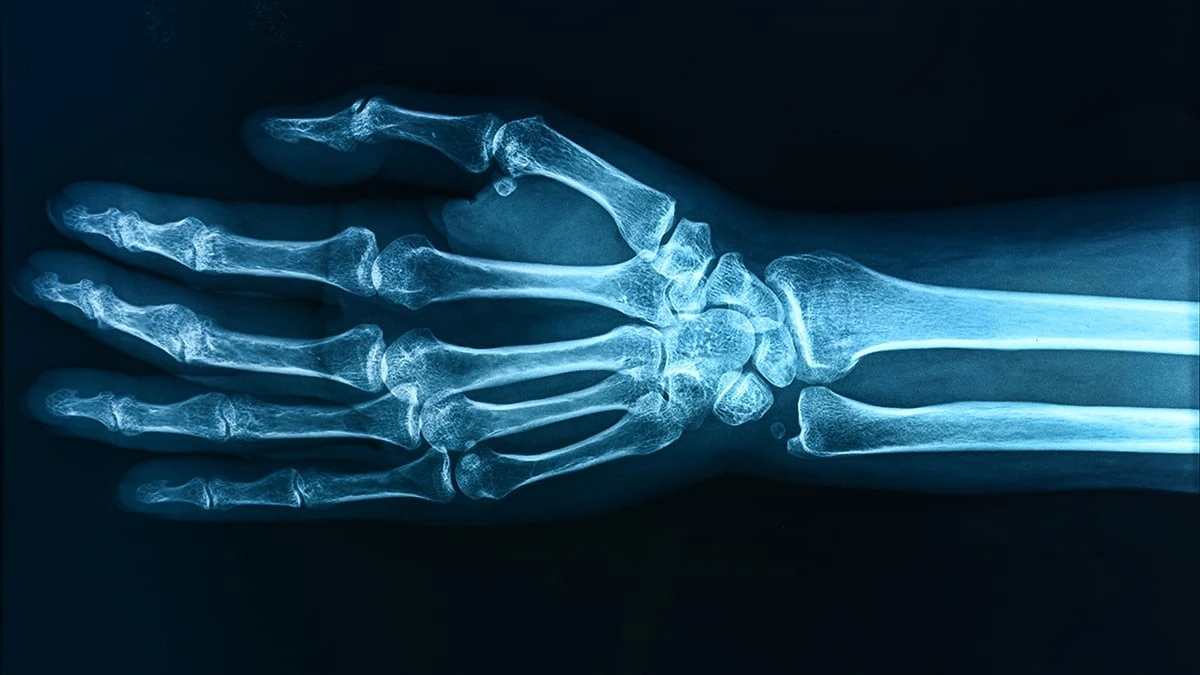

- Wykryto wyraźny związek między wyższym poziomem substancji PFOA a niższą gęstością kości u 12-latków.

- Szacuje się, że różnica w gęstości kości może przekładać się na nawet 30% wyższe ryzyko złamań w przyszłości.

Dzieciństwo to kluczowy czas budowania fizycznego „fundamentu” na całe życie. Jeśli gęstość kości jest niska w młodym wieku, rośnie ryzyko osteoporozy i poważnych kontuzji w dorosłości. Mechanizm prawdopodobnie wiąże się z zaburzeniami gospodarki witaminą D, która – jak wiemy – jest niezbędna do prawidłowego rozwoju szkieletu.